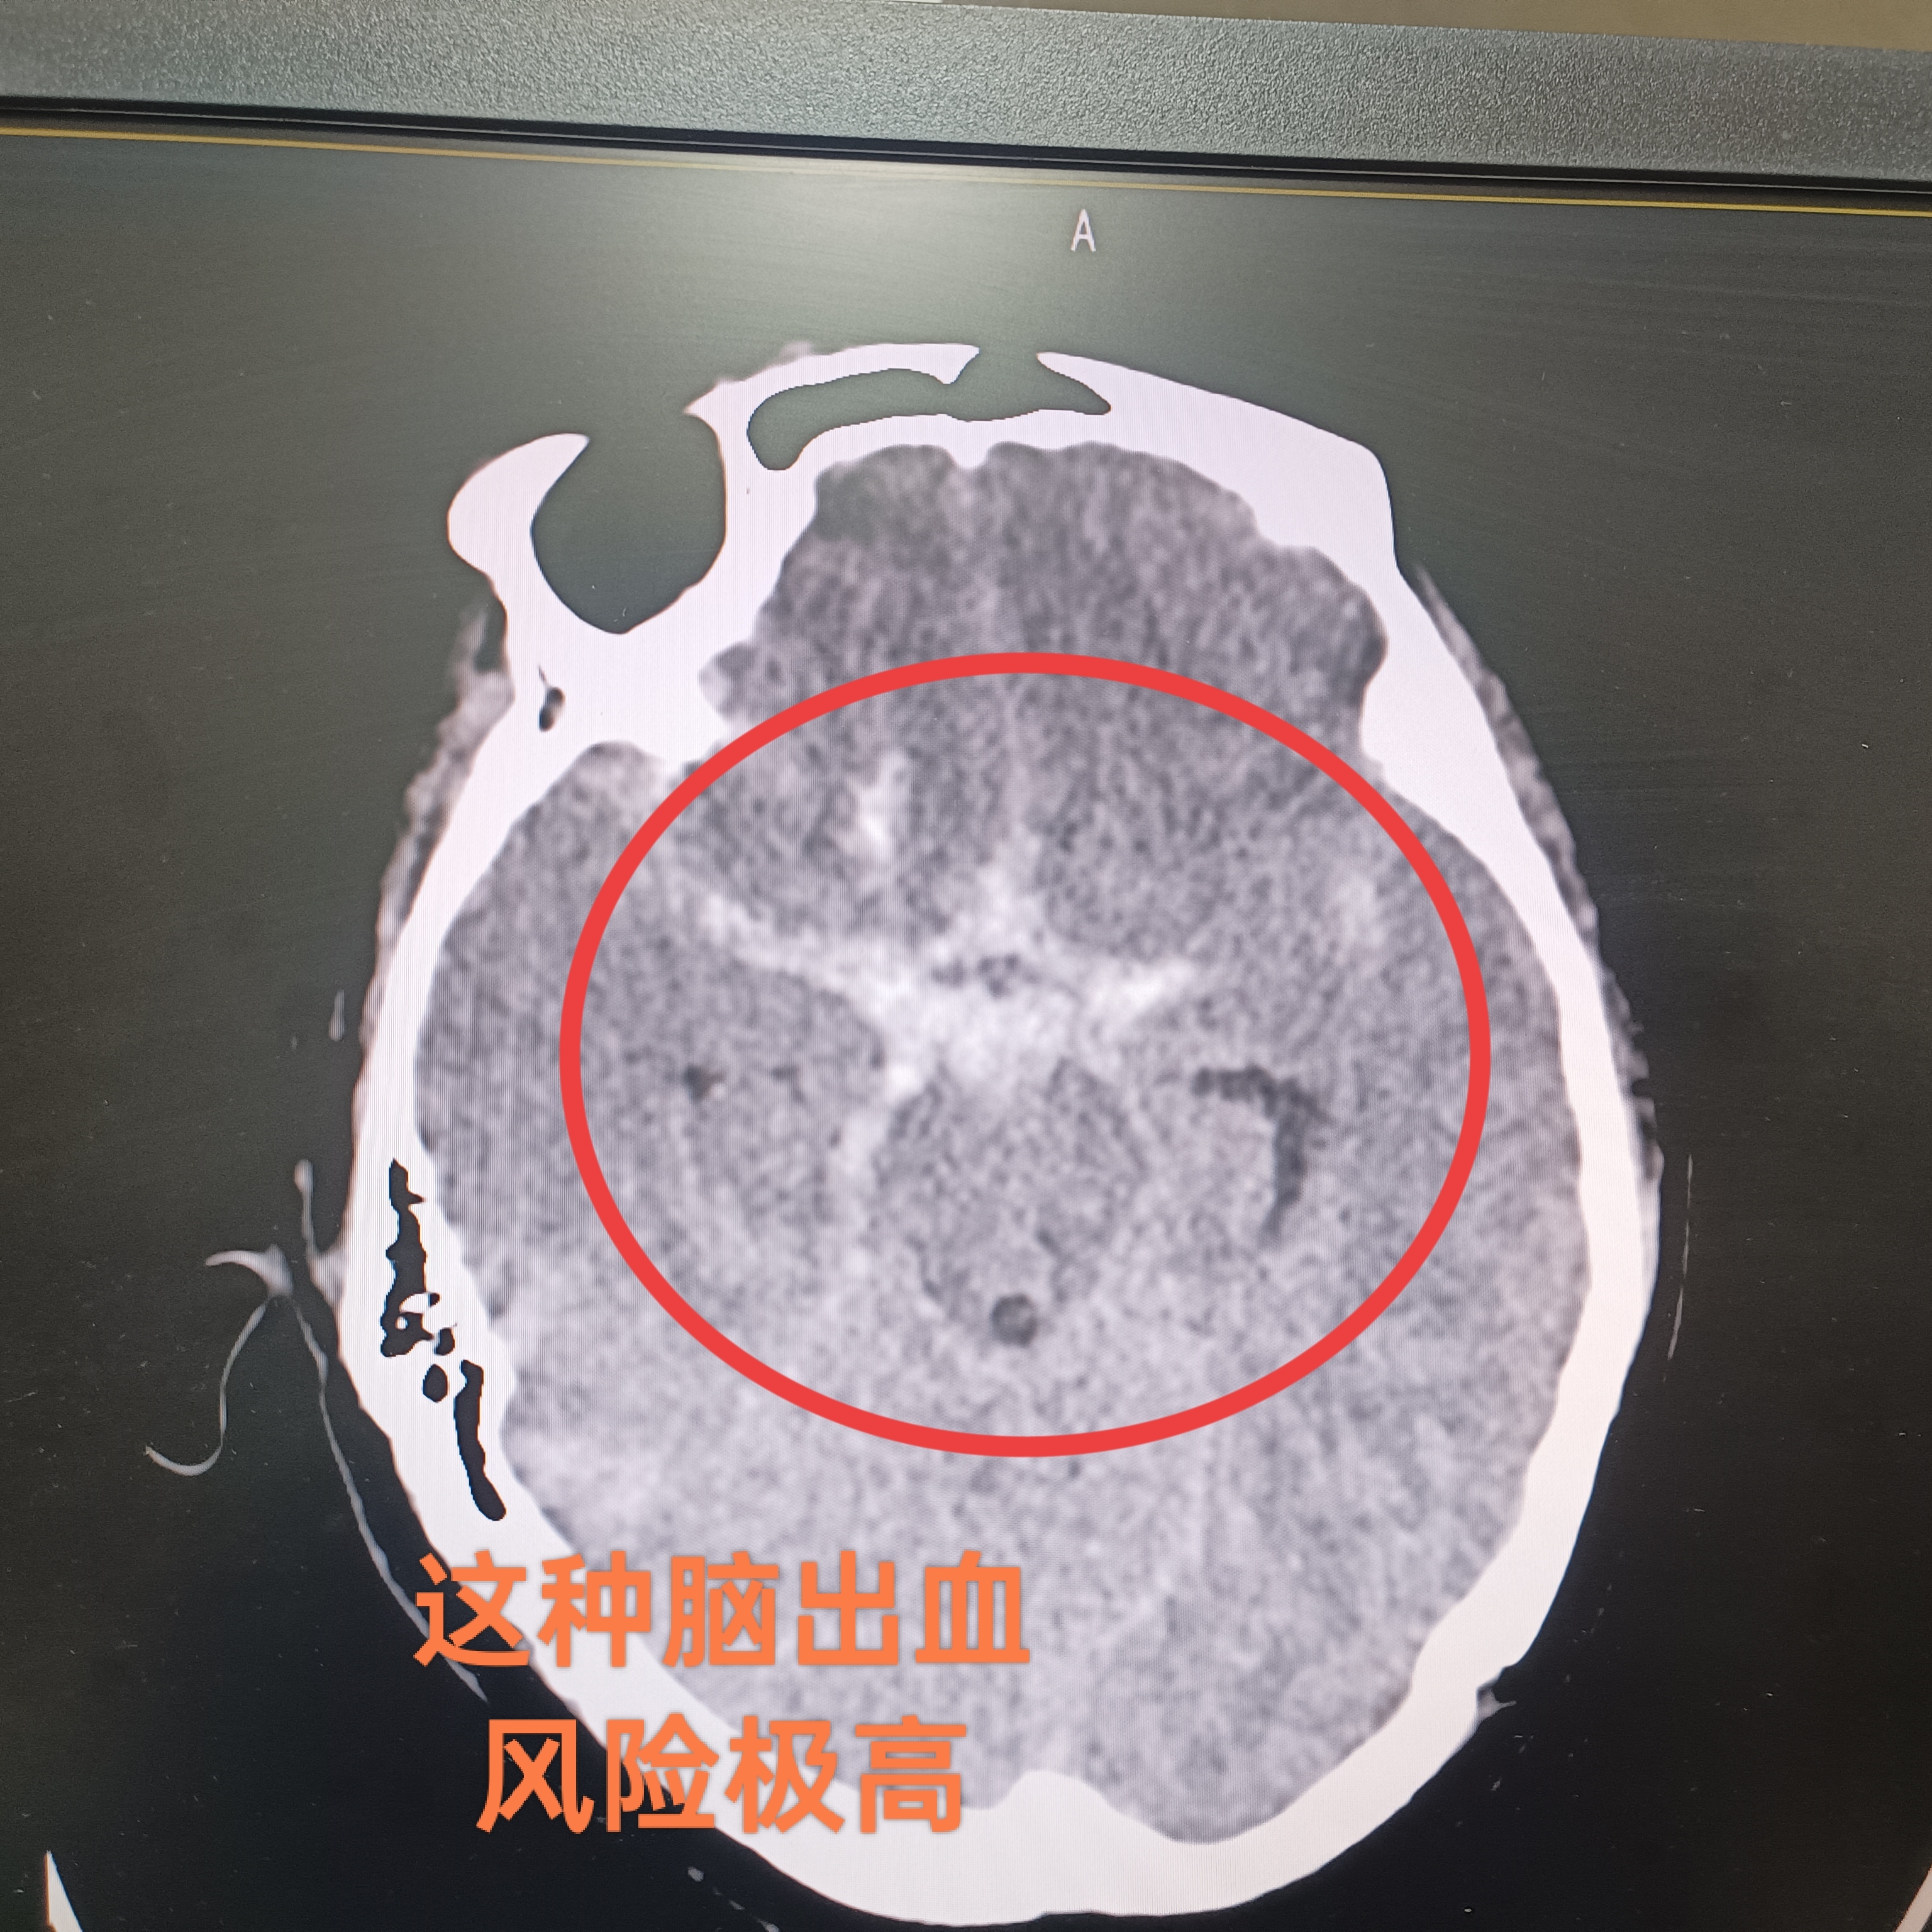

顱內(nèi)動脈瘤:破裂前后治療的天壤之別!?????顱內(nèi)動脈瘤就像一顆隱藏在大腦中的“不定時炸彈”。破裂之前進行治療與破裂之后治療有著天壤之別。????在破裂之前,醫(yī)生可以有充分的時間進行全面評估和準備。通過腦血管造影等檢查準確確定動脈瘤的位置、大小、形態(tài)等,選擇合適的治療方法,如介入栓塞術(shù)或開顱夾閉術(shù)。治療風險相對較低,患者術(shù)后恢復也往往較為順利,能夠最大程度地保護神經(jīng)功能,避免嚴重并發(fā)癥的發(fā)生。?????然而,一旦動脈瘤破裂,情況則急轉(zhuǎn)直下?;颊邥话l(fā)劇烈頭痛、嘔吐,甚至昏迷。破裂后的出血會對腦組織造成嚴重的壓迫和損傷,引發(fā)腦水腫、腦血管痙攣等一系列危及生命的并發(fā)癥。此時進行治療,難度大幅增加,患者的死亡率和致殘率也急劇上升。即使經(jīng)過全力搶救,患者也可能遺留嚴重的神經(jīng)功能障礙,如偏癱、失語、認知障礙等,給患者及其家庭帶來沉重的打擊。???因此,對于顱內(nèi)動脈瘤,早期發(fā)現(xiàn)、早期治療至關(guān)重要,切不可掉以輕心,以免造成不可挽回的后果。